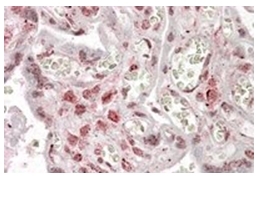

- Main image

- Experimental details

- Staining of paraffin embedded Human Placenta using MLX Antibody Cat.-No AP31860PU-N at 3.8 µg/ml. Steamed antigen retrieval with citrate buffer pH 6, AP-staining.